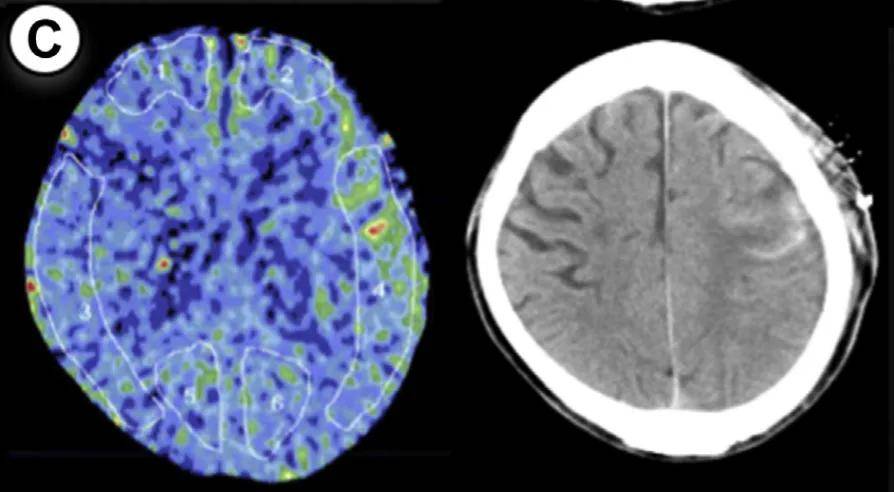

病例1:55岁男性,右侧大脑手术。方法1 rCBF增加率47%,方法2达55%(超过50%阈值)。术后第3天未维持镇静,第2天发生脑出血,改良Rankin量表评分恶化。

病例2:55岁男性,左侧大脑手术。方法1和方法2的rCBF增加率均为50%,达到预警阈值。术后第1天发现少量蛛网膜下腔出血(SAH),因术前规划2天镇静和血压控制,未出现神经功能缺损。

病例3:44岁女性,左侧大脑手术。方法1 rCBF增加率100%,方法2达114%,术后第2天脑出血。因术后及时给予1天镇静和严格控压,未遗留神经功能问题。

病例4:49岁女性,右侧大脑手术。方法1 rCBF增加率89%,方法2达133%,术后第5天发现硬膜下血肿合并蛛网膜下腔出血。

病例5:49岁男性,左侧大脑手术。方法1 rCBF增加率78%,方法2高达149%,术后第2天发现少量蛛网膜下腔出血。术后给予1天持续镇静,出血未扩大。

病例6:26岁男性,右侧大脑手术。方法1 rCBF增加率63%,方法2达72%,术后第2天发现硬膜下血肿合并蛛网膜下腔出血。术后1天镇静干预后出血吸收。

病例7:35岁女性,左侧大脑手术。方法1 rCBF增加率77%,方法2达67%,术后第2天发现出血合并脑室内出血。因术前知晓rCBF超标,提前规划镇静干预。

7个病例年龄范围25-55岁(无儿童),出血类型包括脑出血(ICH)、蛛网膜下腔出血(SAH)、硬膜下血肿(SDH)及混合出血,发病时间术后1-5天。所有患者rCBF增加率均≥30%(方法1)或≥50%(方法2),证实这两个阈值的预警价值。